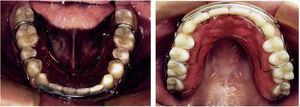

Análisis intraoral. Se observan los incisivos laterales microdónticos y la desviación de la línea media dental inferior con respecto a la línea media dental superior 0.5mm a la izquierda, así como clase I molar y canina bilateral, apiñamiento leve inferior y la forma de arcadas (Figura 2).

Resultados del tratamiento. En las fotografías extraorales finales podemos ver que se mantiene un paciente dolicofacial, un perfil adecuado. Se muestra un adecuado overbite y overjet, líneas medias coincidentes, clase I canina, clase I molar y adecuada intercuspidación, se observa la realización de restauraciones directas en resina en los laterales superiores. A nivel oclusal presenta una continuidad y forma oval a nivel maxilar y mandibular. Se colocaron retenedores circunferenciales superior e inferior (Figuras 9 a 11).